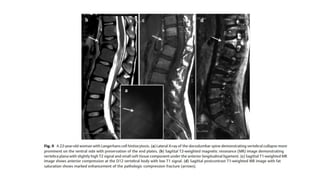

Histiocitosis de células de Langerhans

La histiocitosis de células de Langerhans (HCL) es una lesión benigna que puede afectan la columna vertebral en el

6% de los casos. Los segmentos torácicos son más más comúnmente afectados que las regiones lumbar y cervical.

Radiológicamente, la HCL demuestra lesiones líticas focales que puede progresar a un colapso vertebral uniforme

formando la apariencia clásica de "vértebra plana", que se ve en sólo el 15% de los casos.

Normalmente, las placas de los extremos se conservan.

El colapso vertebral parcial y el reemplazo focal de la médula pueden también ocurren. La apariencia de la HCL en la

resonancia magnética revela áreas de baja señal reemplazo de médula ósea en las imágenes de RM ponderadas en

T1 y de alta intensidad de señal en las imágenes de RM ponderadas en T2. Los hallazgos pueden ser muy sutil en

películas simples.